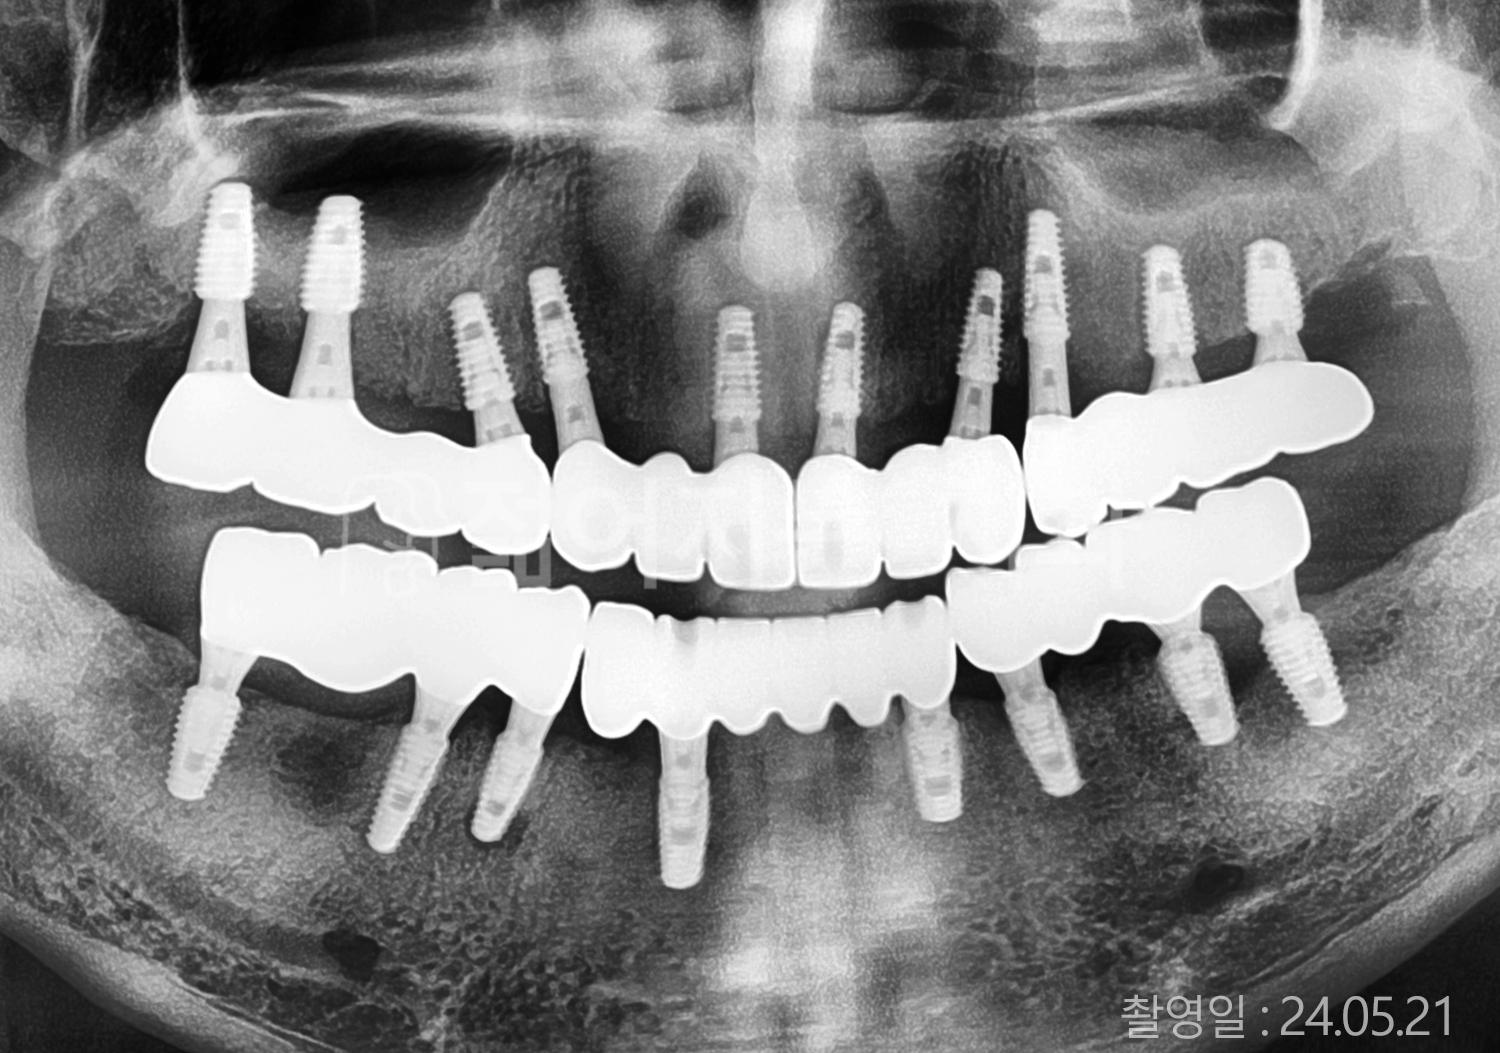

• 70대 고혈압, 당뇨 전체치아 10개 이상 임플란트

• 50대 고혈압, 당뇨 전체치아 10개 이상 임플란트

• 60대 고혈압, 당뇨 전체치아 10개 이상 임플란트

• 50대 전체치아 10개 이상 임플란트

• 70대 당뇨 전체치아 10개 이상 임플란트

• 80대 전체치아 10개 이상 임플란트

• 40대 전체치아 10개 이상 임플란트

• 60대 고협압, 고지혈증 전체치아 10개 이상 임플란트

• 60대 전체치아 10개 이상 임플란트